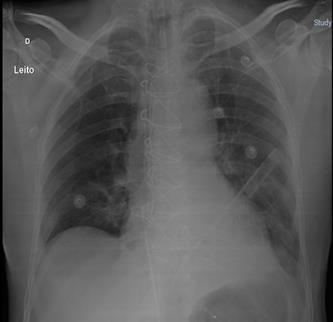

In the intensive care unit, he progressed without the need for vasoactive drugs, being extubated in the first hours after the surgical approach (Figure 1). He was discharged to the infirmary on the 2nd postoperative day, being readmitted to the intensive care unit after 24 hours, with a reduced level of consciousness and desaturation, requiring mechanical ventilatory support. Laboratory tests (Table 1), cultures, radiography (Figure 2) and chest tomography were requested, showing a peripheral ground-glass pattern on CT (Figure 3).

Figure 2 – Chest radiography on the 3rd postoperative day demonstrating bilateral lung opacities